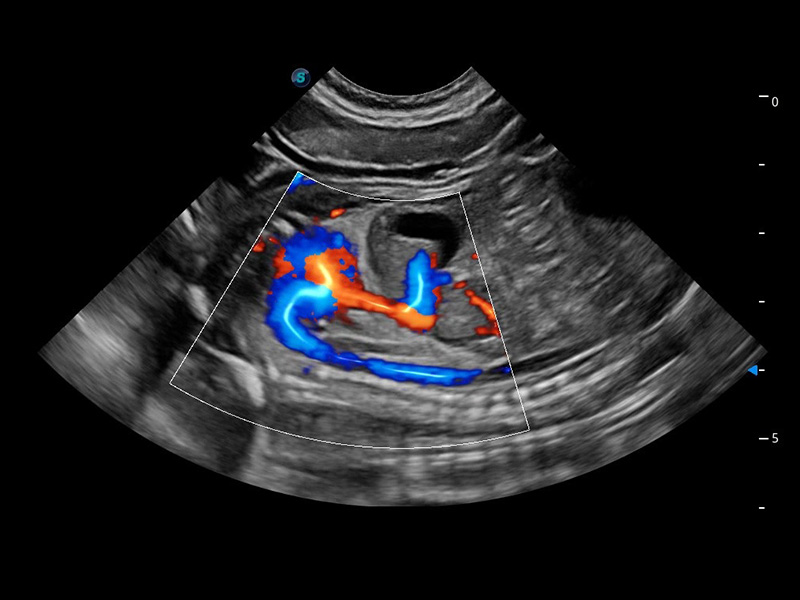

ProPet 60 作为一款高端台式动物超声设备,为动物医生的日常诊断提供了一系列贴合动物临床需求、解决临床实际问题的高级成像功能。凭借全系列高清探头,满足医生对腹部、心脏、生殖、浅表、肌骨等成像的所有需求,切实帮助您提升检查效率,提高诊断信心。

动物是人类最亲密的朋友和最值得信赖的伙伴。16877太阳集团也一直致力于探索动物专用的超声影像解决方案。 全新推出的ProPet系列,是16877太阳集团在动物超声影像智能化、专业化、精准化的一次跨越式革新。动物不能用言语来表述自己的不适,通过超声影像,ProPet系列搭建了动物医生与不同物种沟通的“桥梁”,为动物医生注入了“治愈之力”。